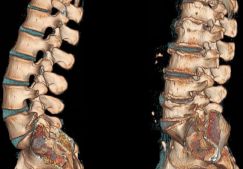

Ревматоидный артрит – хроническое генерализованное аутоиммунное поражение соединительной ткани, поражающее суставы скелета, чаще всего мелкие суставы на руках. Лечение ревматоидного артрита длительное и комплексное, включающее курсы приема нестероидных противовоспалительных средств, гормональных препаратов, цитостатиков. Лечит эту патологию врач-ревматолог. Большое значение имеет также правильный рацион. Диета при ревматоидном артрите не заменяет лечение, но дополняет его и улучшает состояние пациента, увеличивает срок ремиссии и сокращает риск возникновения осложнений.

Для этого заболевания характерно симметричное поражение суставов, как крупных – коленных, локтевых, так и мелких суставов кистей. Суставы кисти поражены в 90% случаев. По мере развития патологии возникает деформация суставов. Кроме сочленений, серопозитивный ревматоидный артрит поражает также соединительную ткань других органов и систем, что вызывает тяжелые нарушения их работы.